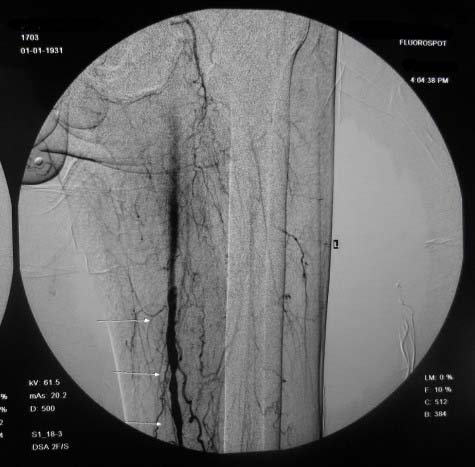

左下肢:

造影方法:取仰卧位,在局麻下,经右股动脉入路,采用改良seldingers技术,置入5f cobra导管于左髂外动脉行dsa,采集速度为2幅/秒,注射速率为6ml/秒,分节段造影;再将导管采用成襻技术放置于右侧髂外动脉,采用左侧同样的方法行dsa,术毕拔管、压迫止血约15分钟,包扎后嘱返病房,术后右足背动脉可扪及搏动。

右侧股浅动脉上、中段多处狭窄,下段闭塞。左侧股浅动脉多处狭窄,国动脉起始部狭窄。可以用球囊扩张配合动脉内溶栓或股浅动脉支架置入。多为糖尿病所致。

双侧股动脉及腘动脉多发狭窄,右股动脉下段闭塞并侧支形成。病变较广泛,球囊可试试,如病人经济不好,最好还是以药物治疗为主。个人意见。